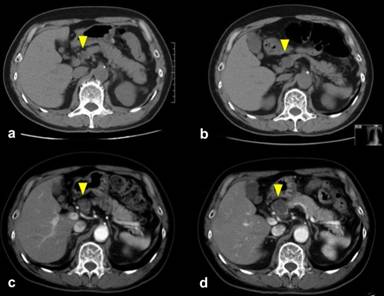

A 67-year-old Asian man with a medical history of lung cancer (well differentiated adenocarcinoma stage I) 14 years previously was followed up at our outpatient clinic after a right lower lobectomy. His serum HIV antibody was negative and there was no other significant medical history. A 20 mm mass in the body of the pancreas, which was a small cystic lesion in 2002, was clearly identified by CT scan and MRI in 2008, 2012, and 2013 respectively (Figures 1 and 2). Subsequent diagnosis of a serous adenoma based on diagnostic imaging and EUS-FNA had been obtained 2 years previously. However, there was a growing tendency, from 20 mm to 42 mm, over the 5-year period, and consequently we decided to resect the lesion. A transition of carcinogenic antigen 19-9 (CA 19-9) during this follow up period is illustrated in Figure 3. The intraoperative frozen section revealed a squamous-lined cyst accompanied by sebaceous glands without any malignant findings. Subsequently, resection of the cyst was performed. Chemical analysis of the cyst fluid was not performed due to an extremely small amount of fluid.

Figure 1. CT scan revealed a cystic lesion at the pancreatic body (yellow arrow head) in 2002 which slowly advanced over the 5 years: 40 mm mass in 2013 (a. 2002; b. 2008; c. 2012; d. 2013). |